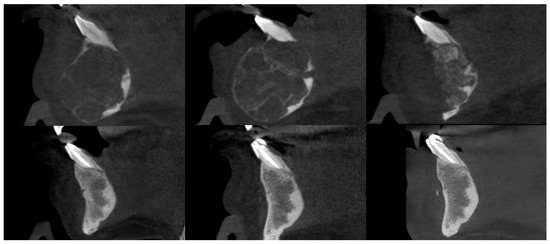

1. Introduction

3. Results

3.2. Injections

3.3. Osteosclerotic Rim (Peripheral Corticalization)